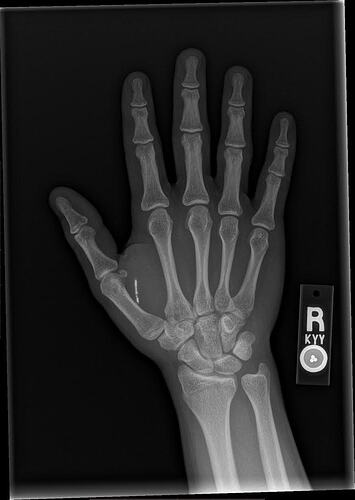

Little Titan update: approaching 2 years with it in and no complaints so far. Nothing strange has happened with it. I’ve bumped it causing significant pain two or three times over the years but I’d compare them to a bad toe stubbing. Painful for a minute, then sore fore less than a day. I can say the sensitivity has slightly decreased since the first 6 months but I suspect my healing tissue was just more sensitive than current tissue. I can still feel the magnets in the airood case in my left pocket as my hand swings by my leg while I walk (that’s one of my favorite things). Here are some x-rays I got this year of both my titan and my NExT installs. NExT chip was installed by a nurse I know Thanksgiving of 2022. No numbing, but the back of the hand wasn’t a very painful place and it went smooth and well.